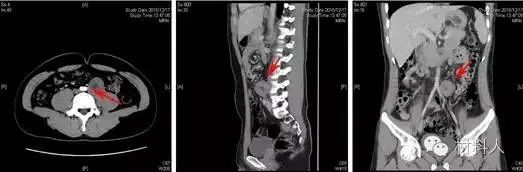

【醫(yī)學(xué)應(yīng)用】2016年1月,北京清華長庚醫(yī)院神經(jīng)外科主任王貴懷教授于神經(jīng)外科上演了一幕“刀尖上的華爾茲”,他利用3D打印技術(shù),“克隆”患者病變部位腰椎模型,精準(zhǔn)地呈現(xiàn)了患者腫瘤與椎體、血管及輸尿管的分布和形態(tài),精準(zhǔn)實施腫瘤切除手術(shù)。